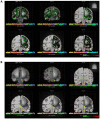

Infection by the severe acute respiratory syndrome (SARS) coronavirus‑2 (SARS‑CoV‑2) is the cause of the new viral infectious disease (coronavirus disease 2019; COVID‑19). Emerging evidence indicates that COVID‑19 may be associated with a wide spectrum of neurological symptoms and complications with central nervous system (CNS) involvement. It is now well‑established that entry of SARS‑CoV‑2 into host cells is facilitated by its spike proteins mainly through binding to the angiotensin‑converting enzyme 2 (ACE‑2). Preclinical studies have suggested that neuropilin‑1 (NRP1), which is a transmembrane receptor that lacks a cytosolic protein kinase domain and exhibits high expression in the respiratory and olfactory epithelium, may also be implicated in COVID‑19 by enhancing the entry of SARS‑CoV‑2 into the brain through the olfactory epithelium. In the present study, we expand on these findings and demonstrate that the NRP1 is also expressed in the CNS, including olfactory‑related regions such as the olfactory tubercles and paraolfactory gyri. This furthers supports the potential role of NRP1 as an additional SARS‑CoV‑2 infection mediator implicated in the neurologic manifestations of COVID‑19. Accordingly, the neurotropism of SARS‑CoV‑2 via NRP1‑expressing cells in the CNS merits further investigation.